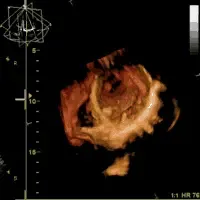

Malattie cardiovascolari

Ischemia, arteriosclerosi, aterosclerosi

Infarto del miocardio

Ipertensione e altre concause

Prevenzione